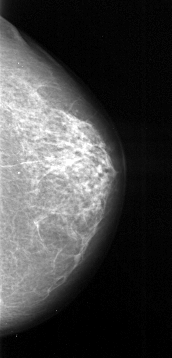

A_1032_1.LEFT_MLO

LEFT_MLO LINES 5371 PIXELS_PER_LINE 2506 BITS_PER_PIXEL 16 RESOLUTION 42 OVERLAY